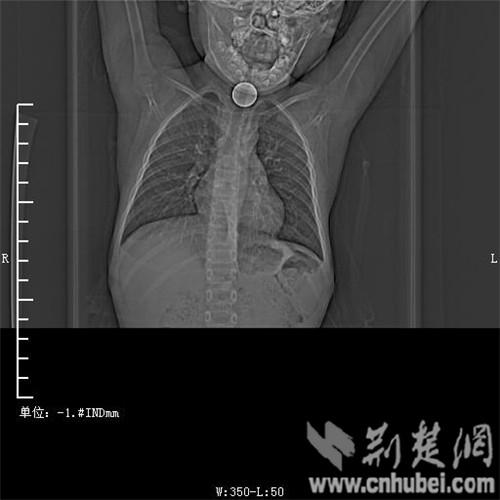

圖為:硬幣卡在了陽(yáng)陽(yáng)的喉部

消化內(nèi)主任方向明告訴記者,孩子送來(lái)時(shí)已經(jīng)是晚上8點(diǎn)15分,醫(yī)護(hù)人員立即給孩子拍胸部CT確定硬幣的位置,8點(diǎn)30分,方向明通過(guò)胃鏡下食管異物取出術(shù),成功的將這枚一元硬幣取了出來(lái)。1月5日上午,陽(yáng)陽(yáng)順利出院,醫(yī)生護(hù)士在他出院時(shí)不斷告訴他,以后千萬(wàn)不要吞含異物。